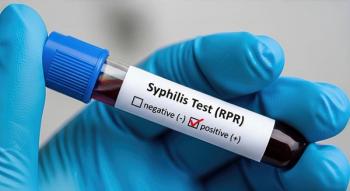

Universal prenatal syphilis screening legislation in Michigan was followed by substantial increases in early third-trimester testing among Medicaid enrollees.